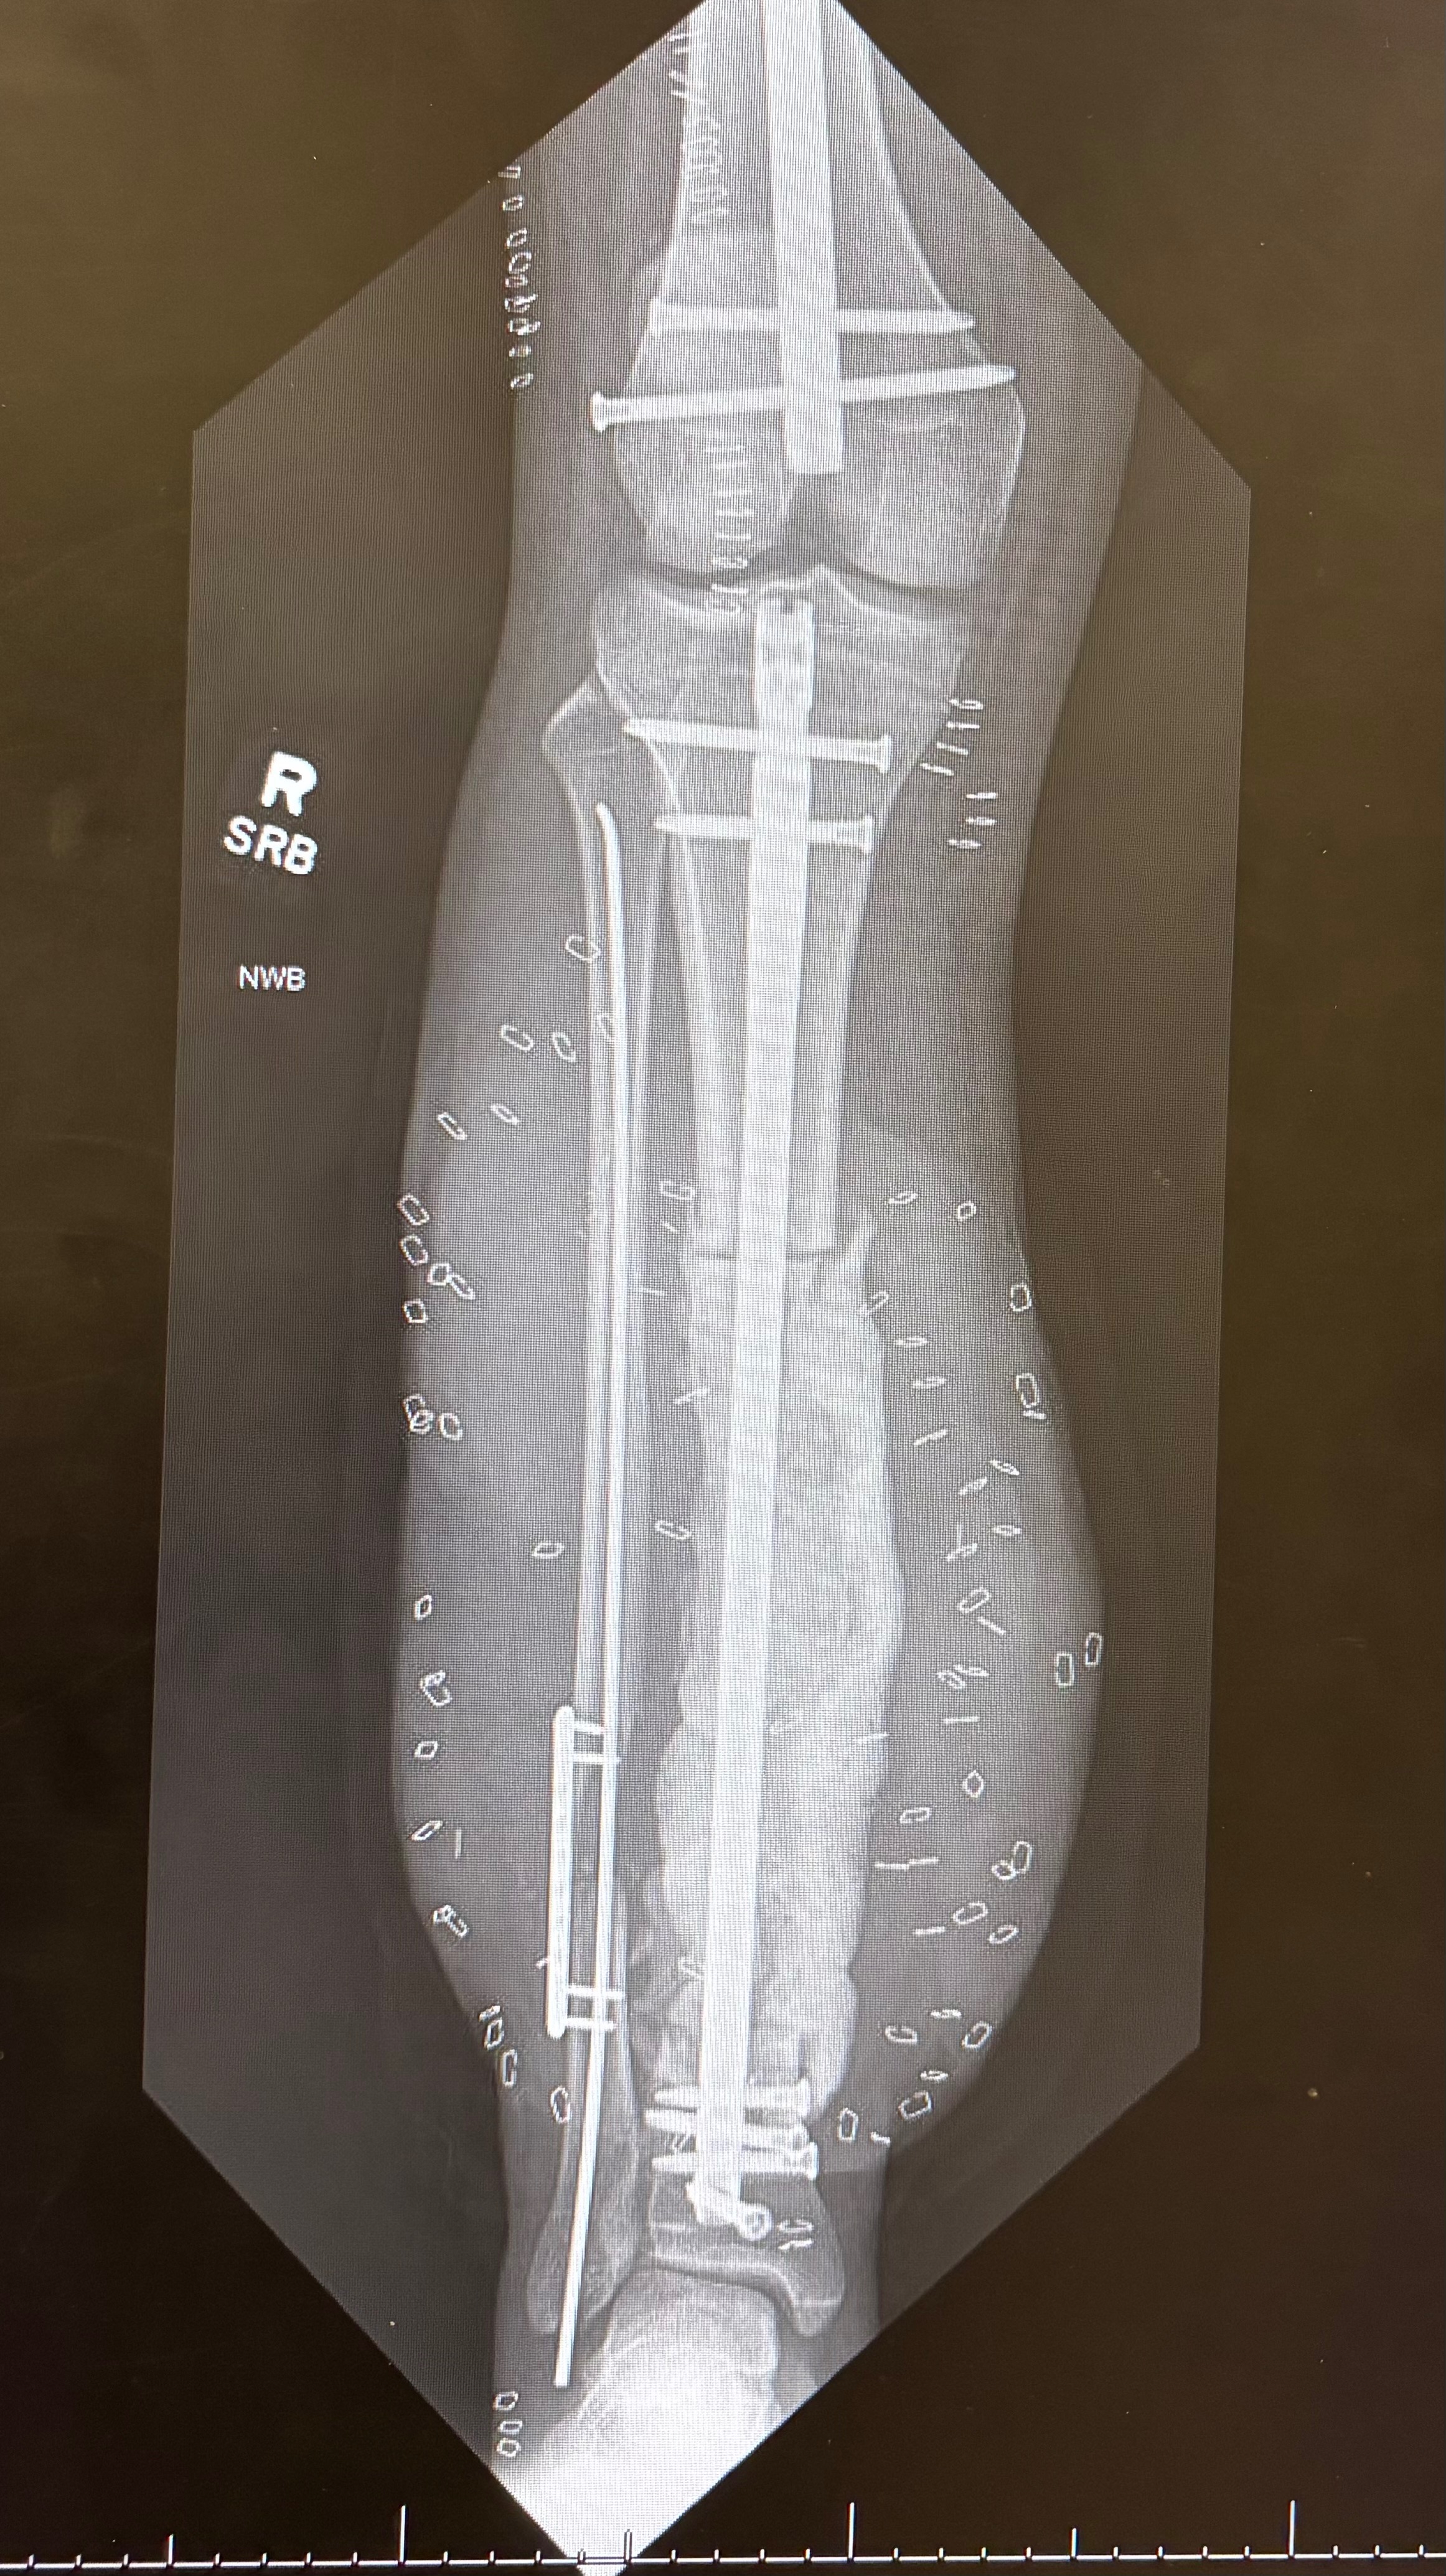

Juan had to undergo four surgeries to save his right leg, he will be having his 5th major surgery on December 31st where one of his surgeons will be doing a bone graft to replace the missing bone from his leg.

The surgeons made a choice to remove a large muscle from his back to use the muscle to create a skin graft as an attempt to save his leg.